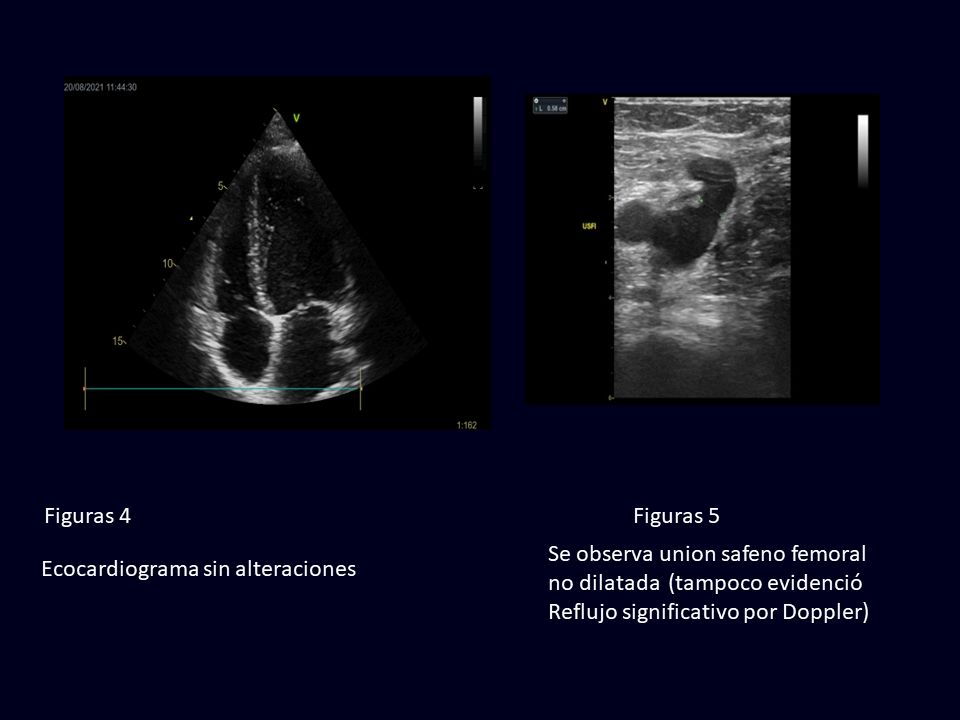

Dicha medida se obtiene mediante métodos de diagnóstico como, por ejemplo, la ecocardiografía. Se considera que la fracción de eyección se encuentra preservada (es decir, es normal) cuando su valor es mayor o igual a 50%. Si sus valores se hallan entre 49% y 41%, se considera fracción de eyección de rango medio, y si su valor es de 40% o inferior, está reducida. El deterioro de la fracción de eyección expresa una alteración en la capacidad de contracción del corazón y es una de las principales causas de la Insuficiencia Cardíaca.